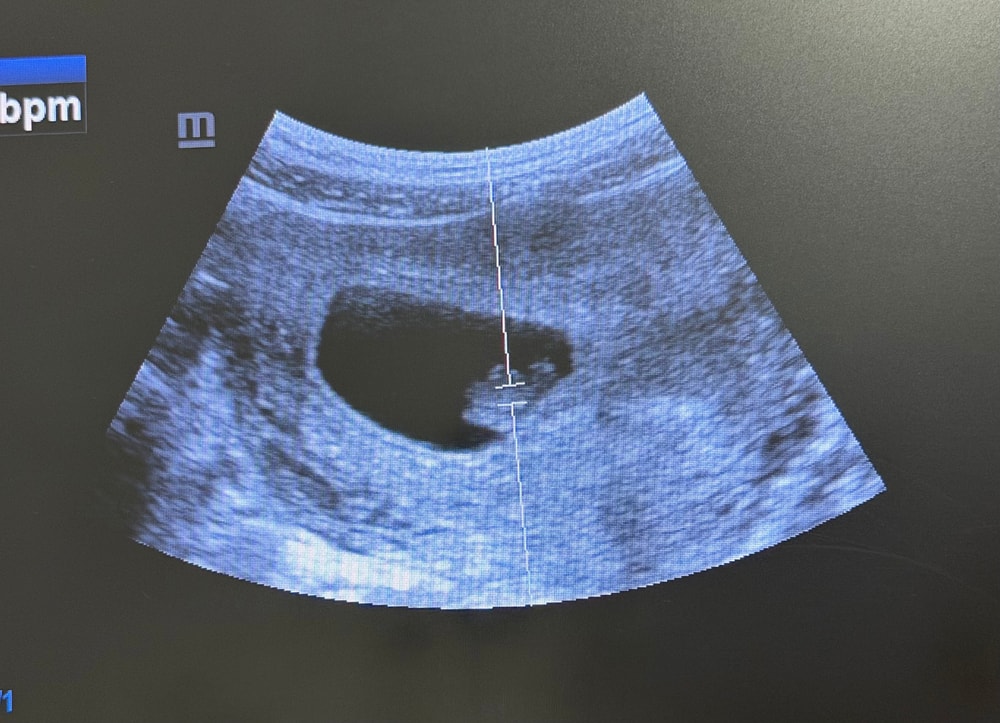

Соня в Благополучная беременность месяц Метод Рамзи Затрудняюсь с категорией Девочки, кто разбирается в методе Рамзи?Узи вагинальное, срок 6 недель и 2 дн Посмотрите еще 20 записей на эту тему Отменить Ответить Ева По методу - девочка:) 11.11.2025 Ответить Ева Ева, 11.11.2025 Ответить Mari Ева, а можете мне тоже посмотреть, пожалуйста 🙏🏻😅 1 узи 6 недель 2 узи 8 недель 11.11.2025 Ответить Ева Mari, у вас девочка по методу, выше скинула референс:) у меня совпало 12.11.2025 Ответить Mari Ева, спасибо большое! Очень надеюсь, что так и есть 😂🙏🏻 12.11.2025 Ответить Соня 11.11.2025 Ответить Шейка на 1 скрининге Зрение у новорожденного Чаты Беременных Выберите чат: Январята-2026 Февралята-2026 Мартята-2026 Апрелята-2026 Майчата-2026 Июнята-2026 Июлята-2026 Августята-2026